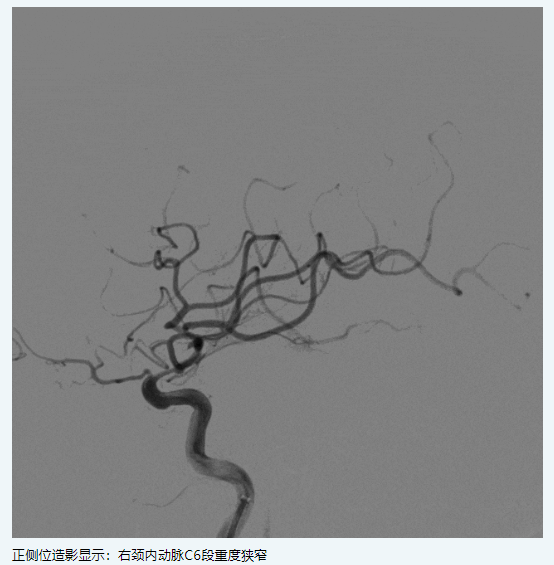

現(xiàn)病史:患者1月前因“左側偏癱,言語含糊”就診我科,溶栓后僅留有言語含糊(NIHSS評分1分)出院,出院診斷為“腦梗死,右側頸內(nèi)動脈C6段重度狹窄,高血壓病3級極高?!?,此次為進一步處理血管回診我科。

二、術前影像

image.png

擬行手術方案:右側頸內(nèi)動脈C6段狹窄球囊擴張+顱內(nèi)藥物洗脫支架植入。

支架:NOVA顱內(nèi)藥物洗脫支架2.25*15mm